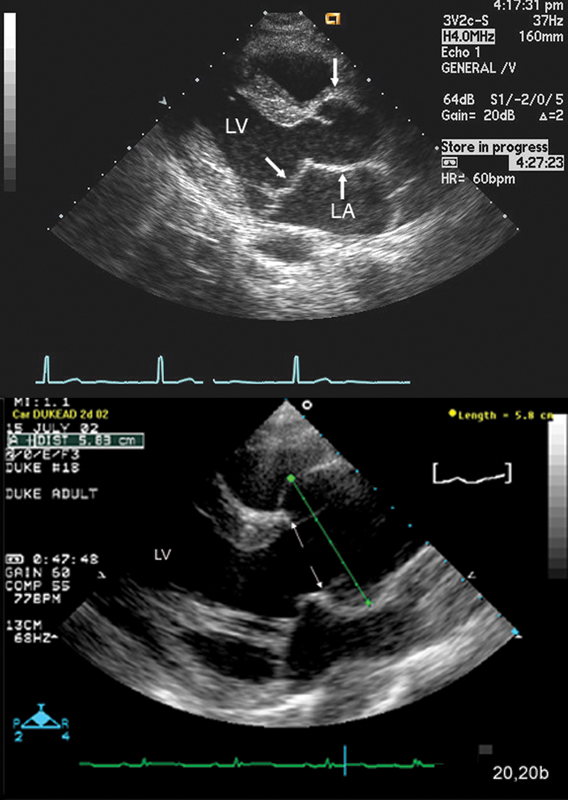

فحوصات تشخيصية لبعض امراض القلب والشرايين التاجية